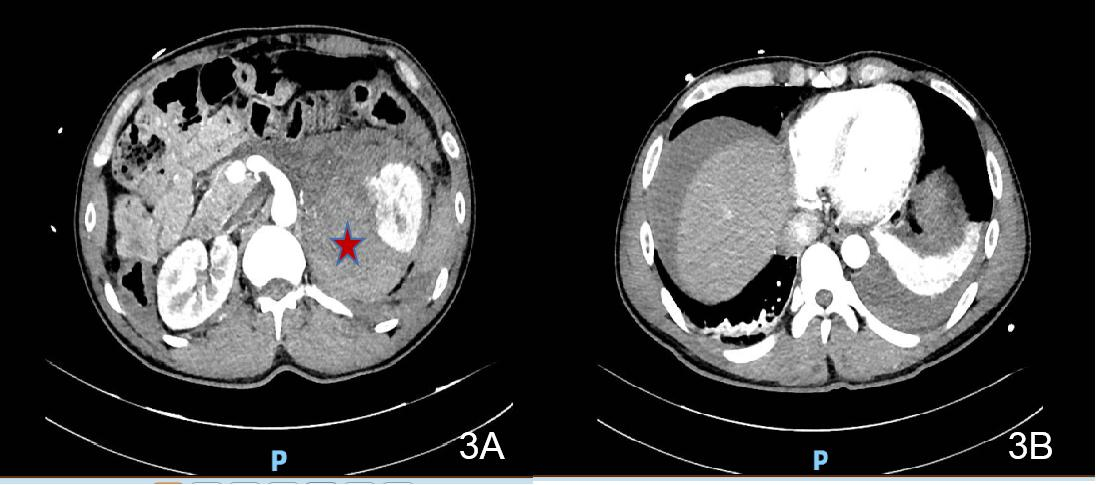

诊治经过如下。入院后查:HGB 81 g/L;生化十项(住院):CR 123.1 μmol/L,GLUC 22.22 mmol/L;心肌损伤标志物:TnI >50.0 ng/mL,MYO 377.45 ng/mL,CKMB Ⅱ 80.86 ng/mL;血气分析:pH 7.361,PCO2 33.5 mmHg,PO2 144.0 mmHg,BEb −5.0 mmol/L。予吸氧、积极补液扩容及输注悬浮红细胞(6U)、控制血糖等治疗。2021-06-18凌晨复查CT提示“左侧肾上腺区占位范围较前相仿,腹腔内积液较前增多”(见图 3)。2021-06-18早上复查BCA示Hb回升至115 g/L。

| 图 3 2021-06-18患者2腹部CT(腹腔积液较前增多) |